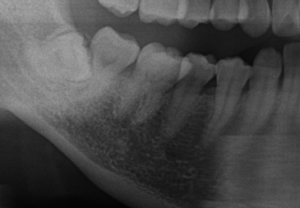

親知らず傾き